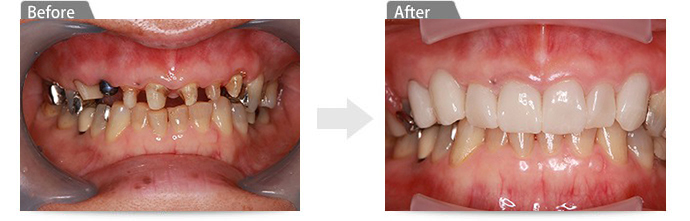

症例9上の歯すべて連続のインプラントでのブリッジ(ガイドを使ったオールオン8)

・上の歯のブリッジが壊れて全部取れたので噛めない(すぐに仮歯が必要)

・残っている歯がもう使える状態ではない(すべて抜歯が必要)

・見た目を綺麗に治したい

・入れ歯にはしたくない - カウンセリングを通して決まったこと

・8本のインプラントを埋入してインプラントブリッジ

・インプラントを行う右上の部位に骨がないので、人工骨にて増骨する(下の写真の赤丸部位)

・見た目が綺麗なまま劣化することのない、ジルコニアで作成したダイアモンドセラミックのブリッジで完成

・痛くない、腫れない治療をご希望のため、ガイドを使ったメス不使用のインプラント手術を採用(そのため " 切らない、縫わないインプラント " が可能)

術前 -

術後 -

ガイドを使用する事により、インプラント8本の埋入位置や平行性などを精密に反映したインプラント手術が行えた。赤丸部位は人工骨にて増骨(ソケットリフト法にてGBR)。 -

(メスを使わない、ガイドを使ったインプラント埋入手術。条件が合えば可能な治療法) -

ガイドを外した状態です。 -

上部構造をAll-on-8で製作した、ダイアモンドセラミックスでのジルコニアブリッジです。

(今回は理由があり、左上奥のインプラントでは埋入未使用)(今回は理由があり、左上奥のインプラントでは埋入未使用) -

治療後の様子です。